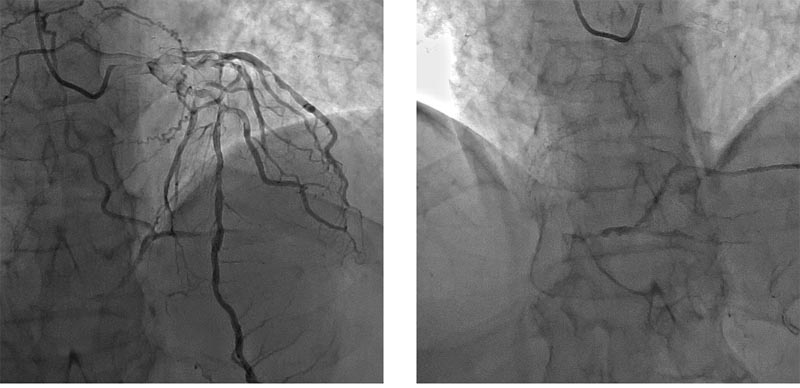

1. Правая коронарная артерия: 1,2,3 сегменты, стеноз с переходом в окклюзию (хроническую, о чем говорят мощная сеть коллатералей и старый инфаркт в анамнезе). Окклюзия с тупым концом (blunt stump), окружена коллатералями (bridging). За хронической окклюзией сегмент визуализируется, но в месте окклюзии отходит одна ветвь больше 1,5 мм, кроме того есть мелкие ветви 0,1,0 по Медина, есть извитость.